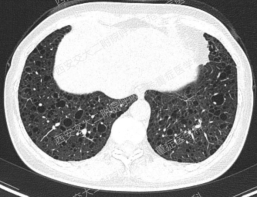

上图所示肺部囊性病变,双侧多发、大小不一,壁薄,形状不规则,呈圆形及扁平状为主,部分融合,分布多在纵隔胸膜下。入院后查血尿粪常规、肝肾功能电解质、凝血功能、血糖血脂心肌酶、BNP、肌钙蛋白正常;红细胞沉降率23mm/h,PCT、CRP正常;TB-spot阳性(阳性对照管反应水平123.49 pg/mL),TB-DNA、PPD试验、痰X-pert、痰涂片、痰培养均阴性;女性肿瘤标志物全套未见异常;结缔组织病相关指标:自身抗体ANA 1:100、CENP B阳性,CCP抗体25.1U/ml(正常参考值<17U/ml),ANCA、抗核抗体谱、体液免疫全套均阴性;血气分析大致正常,肺功能检查: FEV1占预计值78.2%,FEV1/FVC 69.55%,RV/TLC 49.62%,支气管舒张试验阴性,FeNO50 29.2ppb。